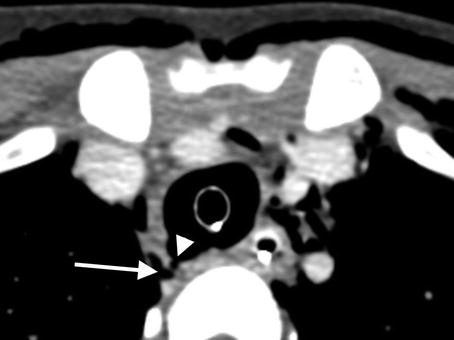

Coronal image from a CT angiogram demonstrates extensive soft tissue emphysema throughout the superficial and deep soft tissues of the neck (arrows) in a patient with a history of benzodiazepine overdose who was intubated in the field

Axial image from the same CT angiogram demonstrates focal contour abnormality within the dorso-lateral quadrant of the upper trachea (arrowhead) with immediately adjacent paratracheal gas (arrow) representing the site of iatrogenic tracheal disruption. Surgical repair of the injured trachea was required